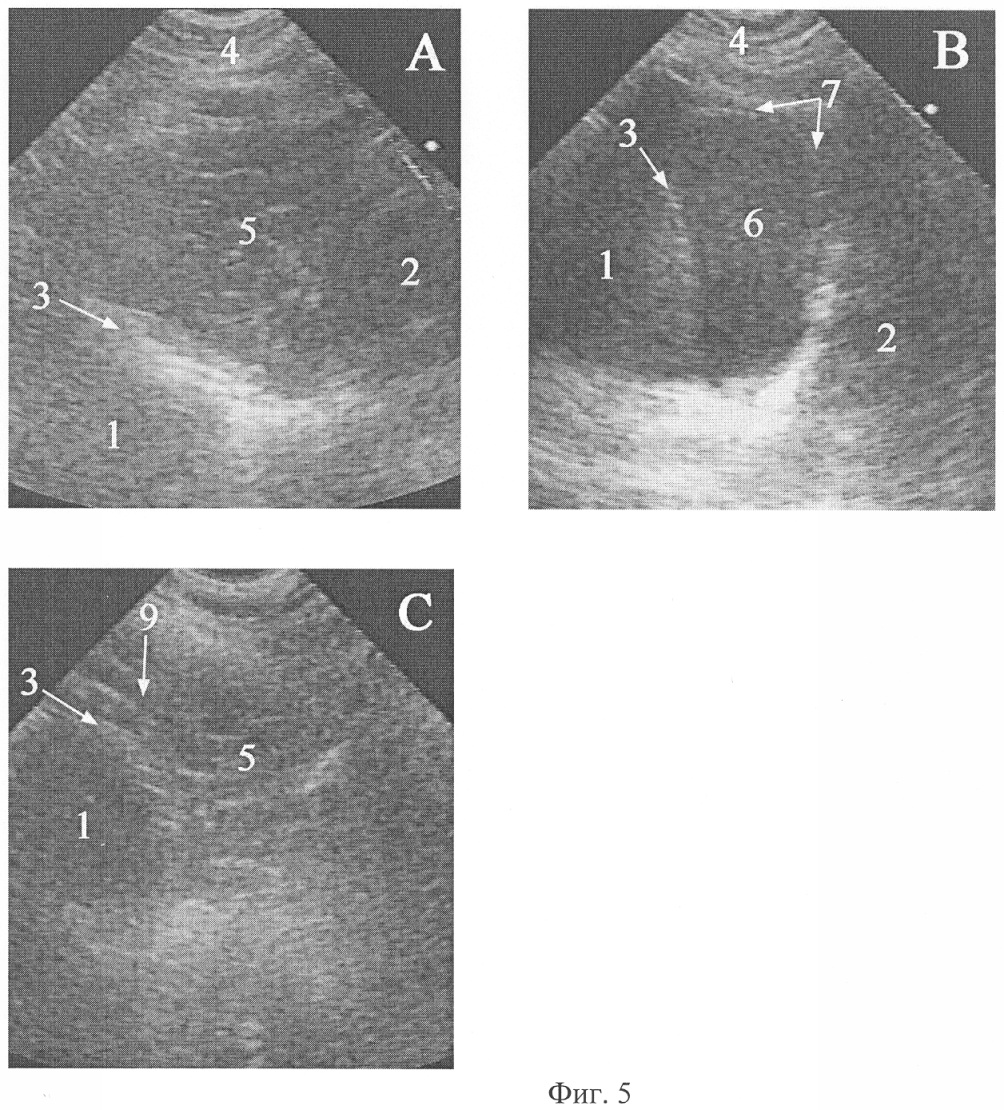

Фиг.5. Эхограммы абдоминомедиастинальной липомы больной В. и целомической кисты перикарда больной Г. (рисунок к клиническому примеру 2).

На фиг.4 и 5 обозначено:

А – поперечное сканирование абдоминомедиастинальной липомы из-под мечевидного отростка с направлением оси сканирования к правому плечу, В – поперечное сканирование целомической кисты перикарда из-под мечевидного отростка с направлением оси сканирования к правому плечу, С – продольное сканирование сообщения абдоминомедиастинальной липомы с предбрюшинной жировой клетчаткой,

1 – печень, 2 – сердце (лоцируется нечетко из-за движения), 3 – медиальная поверхность правого купола диафрагмы, 4 – мягкие ткани грудной стенки, 5 – абдоминомедиастинальная липома, 6 – целомическая киста перикарда, 7 – капсула целомической кисты перикарда, 8 – предбрюшинная жировая клетчатка, 9 – связь абдоминомедиастинальной липомы с предбрюшинной жировой клетчаткой.